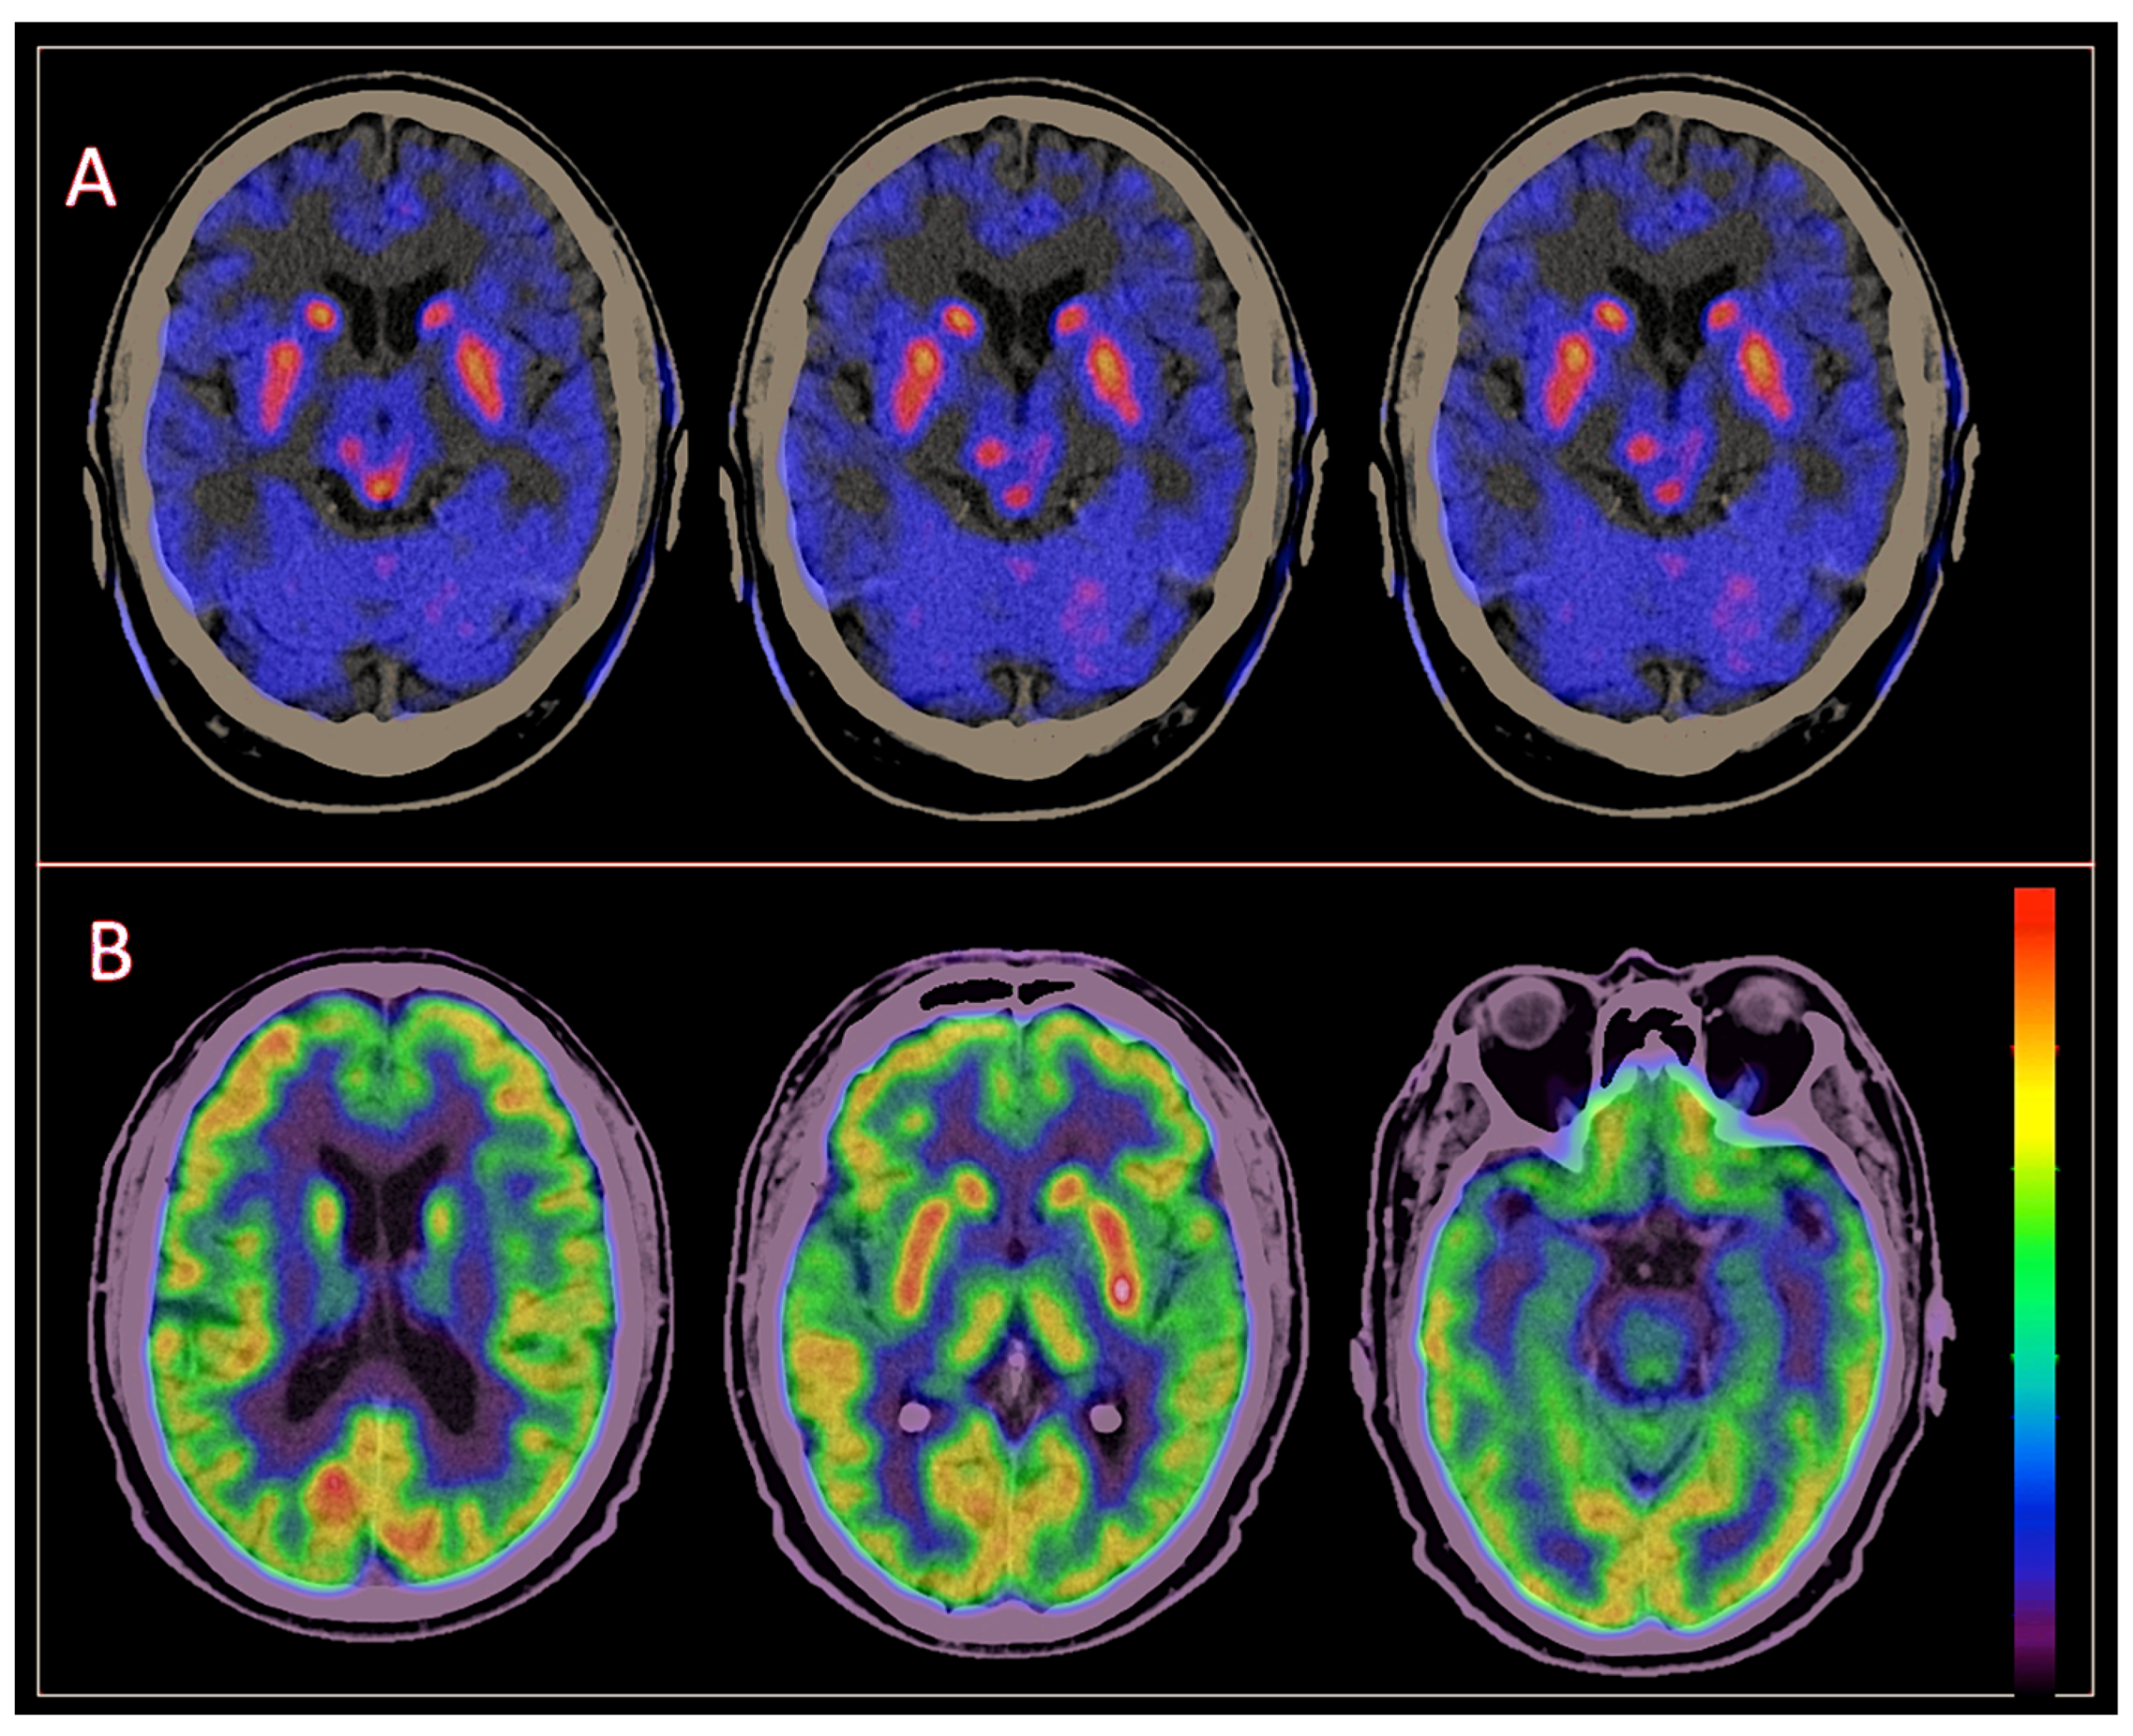

3.2. Brain [18F]DOPA PET/CT Findings

3.3. Brain [18F] FDG PET/CT Findings